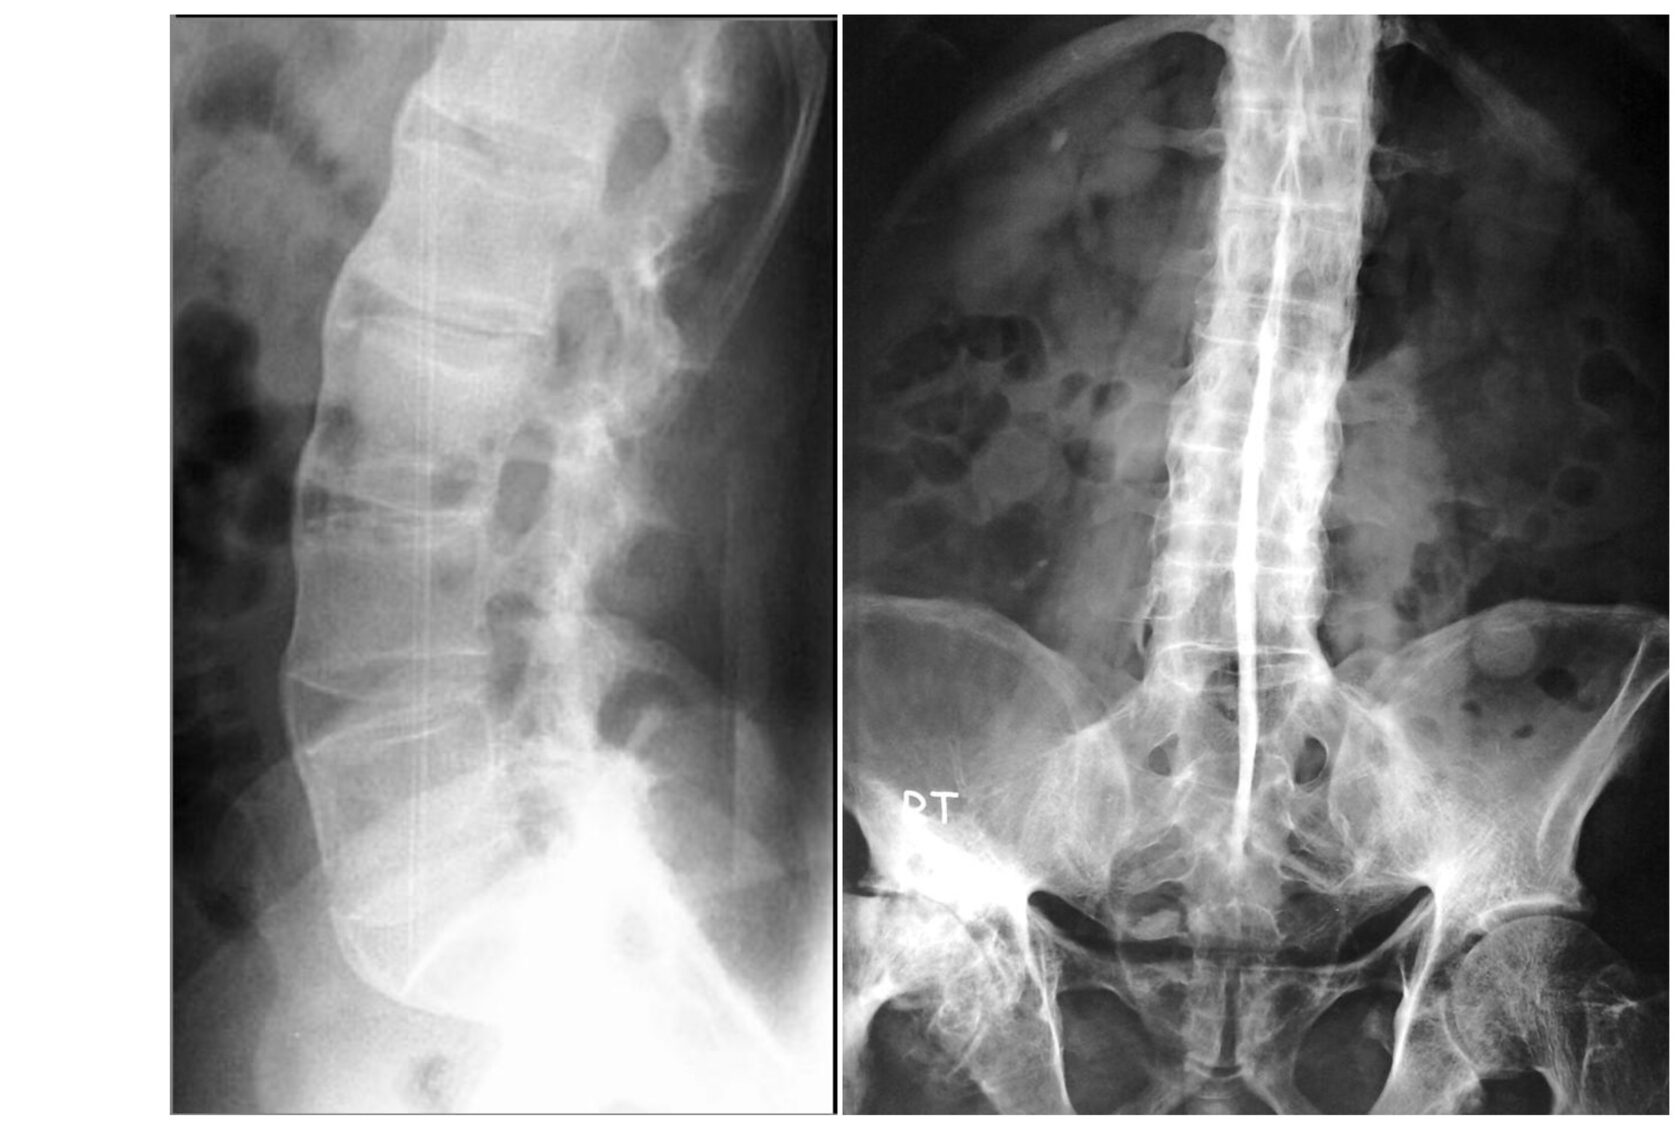

Болезнь Бехтерева Фото 104 фото